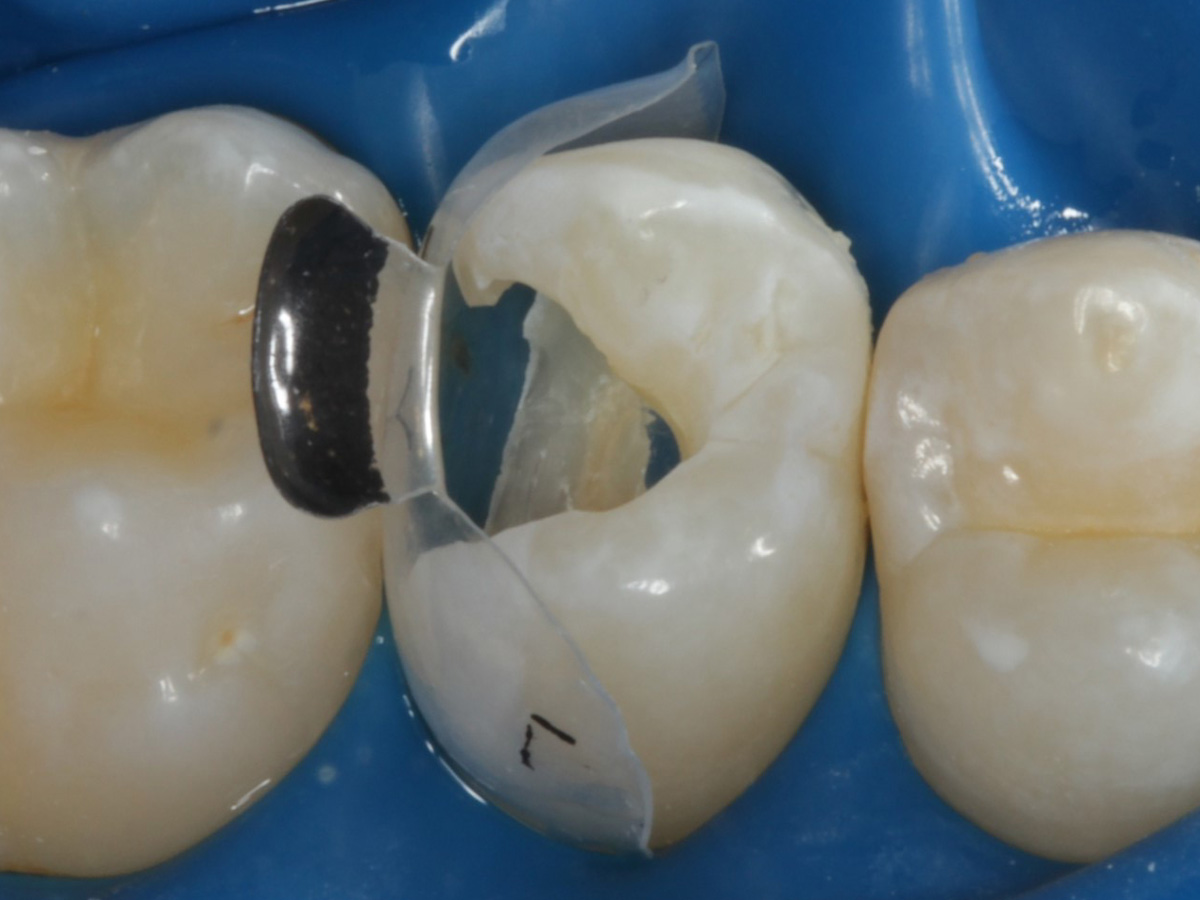

Abbildung 16

Nach Anbringung des Bioclear Twin Ring Universal und Lichthärtung des Einkomponentenadhäsivs

Abbildung 17

Starke Separation der Zähne durch hohe Spannkraft des Twinrings für strammen Kontaktpunkt

Abbildung 18

Bewusst kein Keil zur Vermeidung unerwünschter Matrizenverdrückung

„Erste Portion“ approximal mit fließfähigem Bulkkomposit

Kavität gefüllt (Injektion Moulding: Flowkomposit, erwärmtes Seitenzahnkomposit aus Karpule)